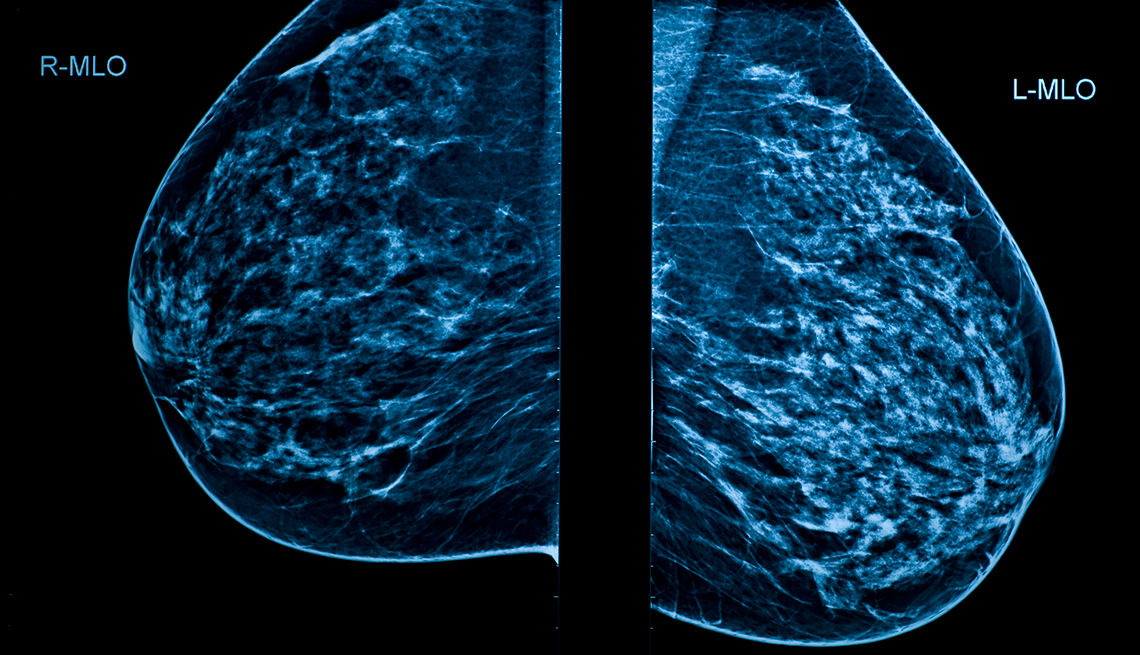

From www.aarp.org

Mammograms When And How Often Should Women Get Them? How Often Should You Have A Mammogram In Canada most guidelines recommend mammography screening every two years for eligible people, with variation across jurisdictions. If you are 75 or older. breast screening guidelines summary. If you are 75 or older, talk to your healthcare provider. Screening average risk people ages 50 to. Talk to your healthcare provider about whether having a. Starting at age 50 and ending. How Often Should You Have A Mammogram In Canada.